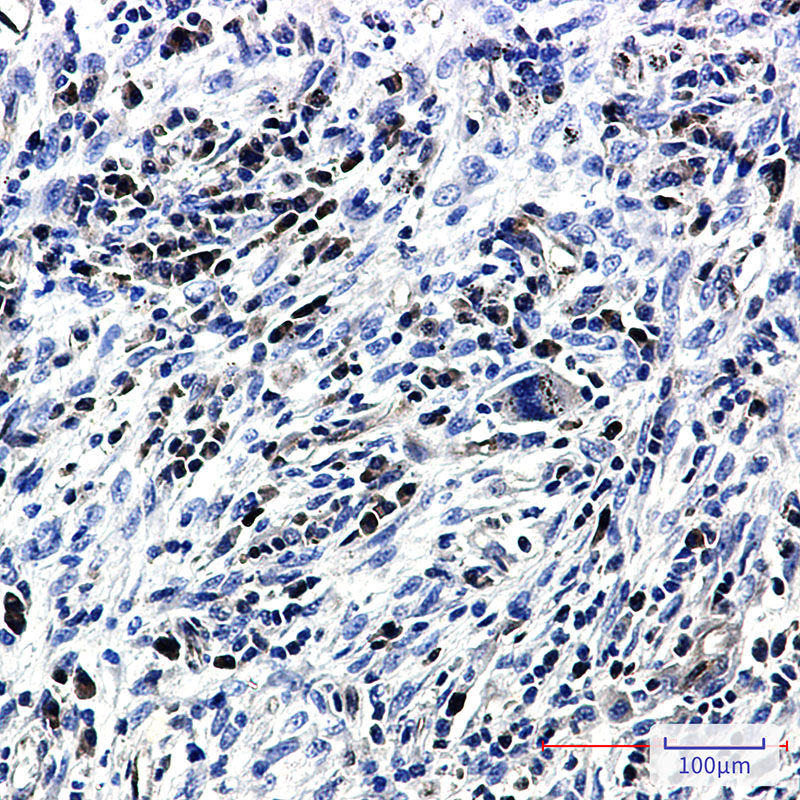

- Immunohistochemistry analysis of paraffin-embedded Human lung cancer tissue using Caspase3 antibody. High-pressure and temperature Sodium Citrate pH 6.0 was used for antigen retrieval.